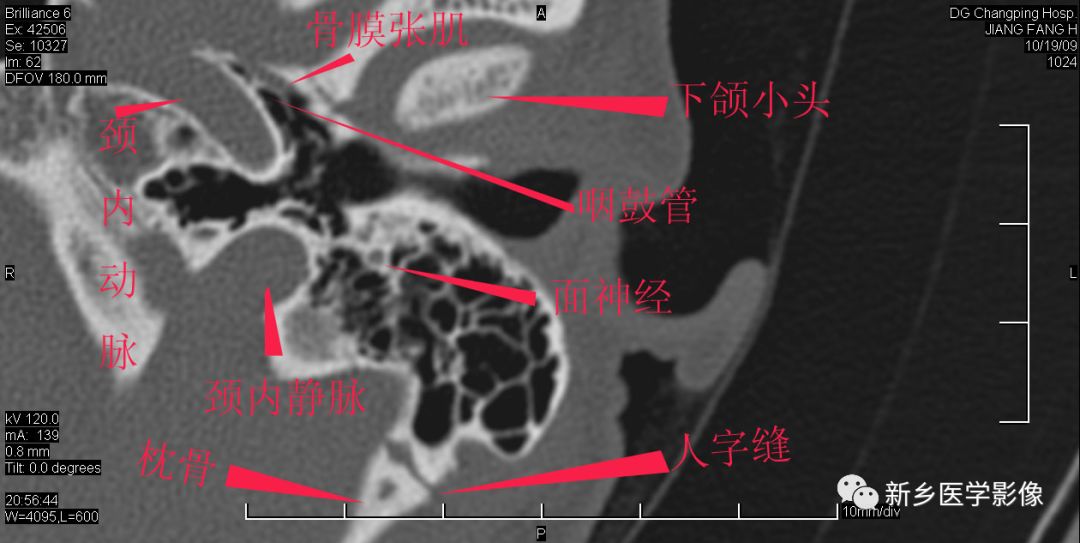

耳部详细解剖纯手工标注